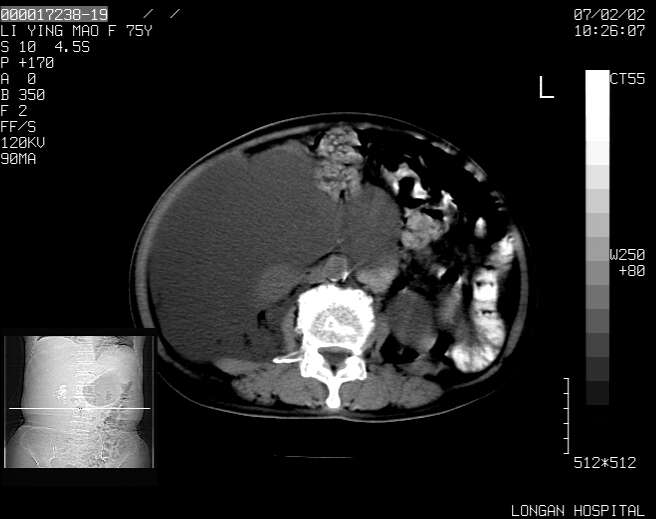

以下是引用dyqct在2007-2-10 8:53:00的发言:[br]考虑:1、肝脏多发囊肿[br] 2、左肾囊肿,右肾多发结石并积水。[br] 3、右胸少量积液。[br] 4、右肾周包裹性积液或淋巴管瘤(有见缝就钻的征象、薄隔、小结节状钙化)?[br] 5、腰椎动脉瘤样骨囊肿?[br] [br] [br]